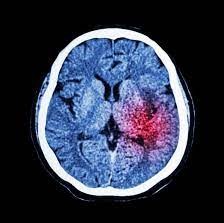

L'accident vasculaire cérébral (AVC) pourrait être limité. En effet, il serait majoritairement causé par 10 facteurs de risque évitables.

Il existerait 10 facteurs de risque évitables de l'accident vasculaire cérébral (AVC), selon les résultats d'une étude publiée par la revue médicale The Lancet. Alcoolisme, hypertension, alimentation de mauvaise qualité... Ces 10 facteurs de risque sont responsables de la majorité (90,7%) de ces accidents et peuvent tous être réduits ou limités.

Les chercheurs de l'Université McMaster (Canada) et ceux de l'Université de Galway (Irlande) ont analysé les données médicales des 20 000 participants de «Interstroke », une étude qui cherche à comprendre les principales causes d'AVC dans différents groupes de population, en fonction de l'âge, du sexe et des deux types d'AVC. Ils ont pu observer 10 causes responsables de la majorité des AVC et calculer leur "part de responsabilité" respectives.

LA PART DE RISQUE ATTRIBUABLE À CHAQUE FACTEUR POUR L'AVC

47,9% pour l'hypertension,

35,8% pour l'inactivité physique,

26,8% pour les lipides

23,2% pour une mauvaise alimentation,

18,6% pour l'obésité,

12,4% pour le tabagisme,

9,1% pour les causes cardiaques,

5,8% pour la consommation d'alcool,

5,8% pour le stress,

3,9% pour le diabète.

Mais les chercheurs rappellent que ces cas de figures sont souvent liés les uns aux autres.

Des résultats à prendre en compte, car l'AVC est une maladie qui atteint en moyenne 130 000 individus par an en France, faisant 33 000 décès et 77 000 victimes souffrant toute leur vie d'aphasie (perte de la capacité à parler, à comprendre des messages écrits) et de problèmes de mémoire.